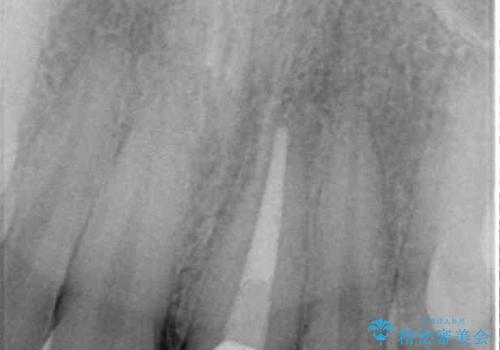

- 神経を取り除いたことで変色した前歯を気にして来院された患者様です。

根管治療はやり直さずに、ファイバーポストを使用した土台を植立してオールセラミッククラウンにて補綴することとしました。

神経を取り除いた歯は時間とともに変色してきます。

クリーニングやホワイトニングでは改善できないため、オールセラミッククラウンなどによる補綴治療が必要となります。